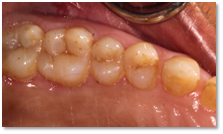

![]() | ![]() |

| Before and after surgery to reshape gums | X-ray showing results before and after bone graft surgery |